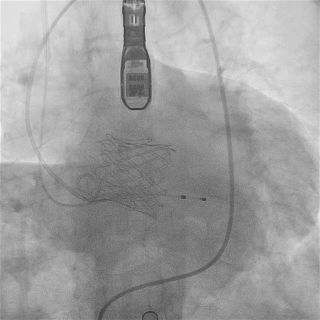

截止目前,臨床試驗進展順利,入組已接近尾聲。中期分析顯示手術成功率和安全性指標均符合預期標準。

瓣膜功能、形態良好,未見反流